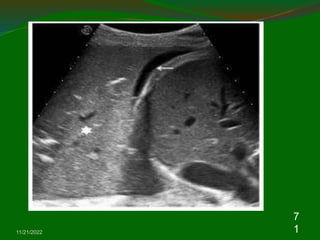

Consolidation

 Irregular hypoechic area of varying size and

shape.

 Echotexure can appear homogenous or

inhomogenous.

 The most common sonographic feature is the

air bronchogram which is characterized by lens

shaped internal echoes within hypodene area

or echogenic lines.